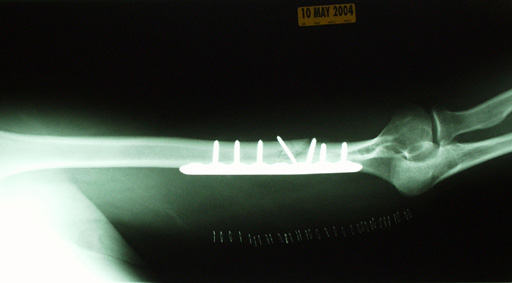

Two weeks after the surgery, I went in for a follow-up exam and more X-rays.

I like this image because it shows a screw which appears to be free-floating. This screw actually holds the two sections of bone together, and is the one screw that was not intended to secure the bone to the plate.

If there is popular demand, I can take a photo of what the incision/scar looks like now, 18 years after the ordeal. The plate and all seven screws are still in there, and probably always will be. Yup, I’m a cyborg.